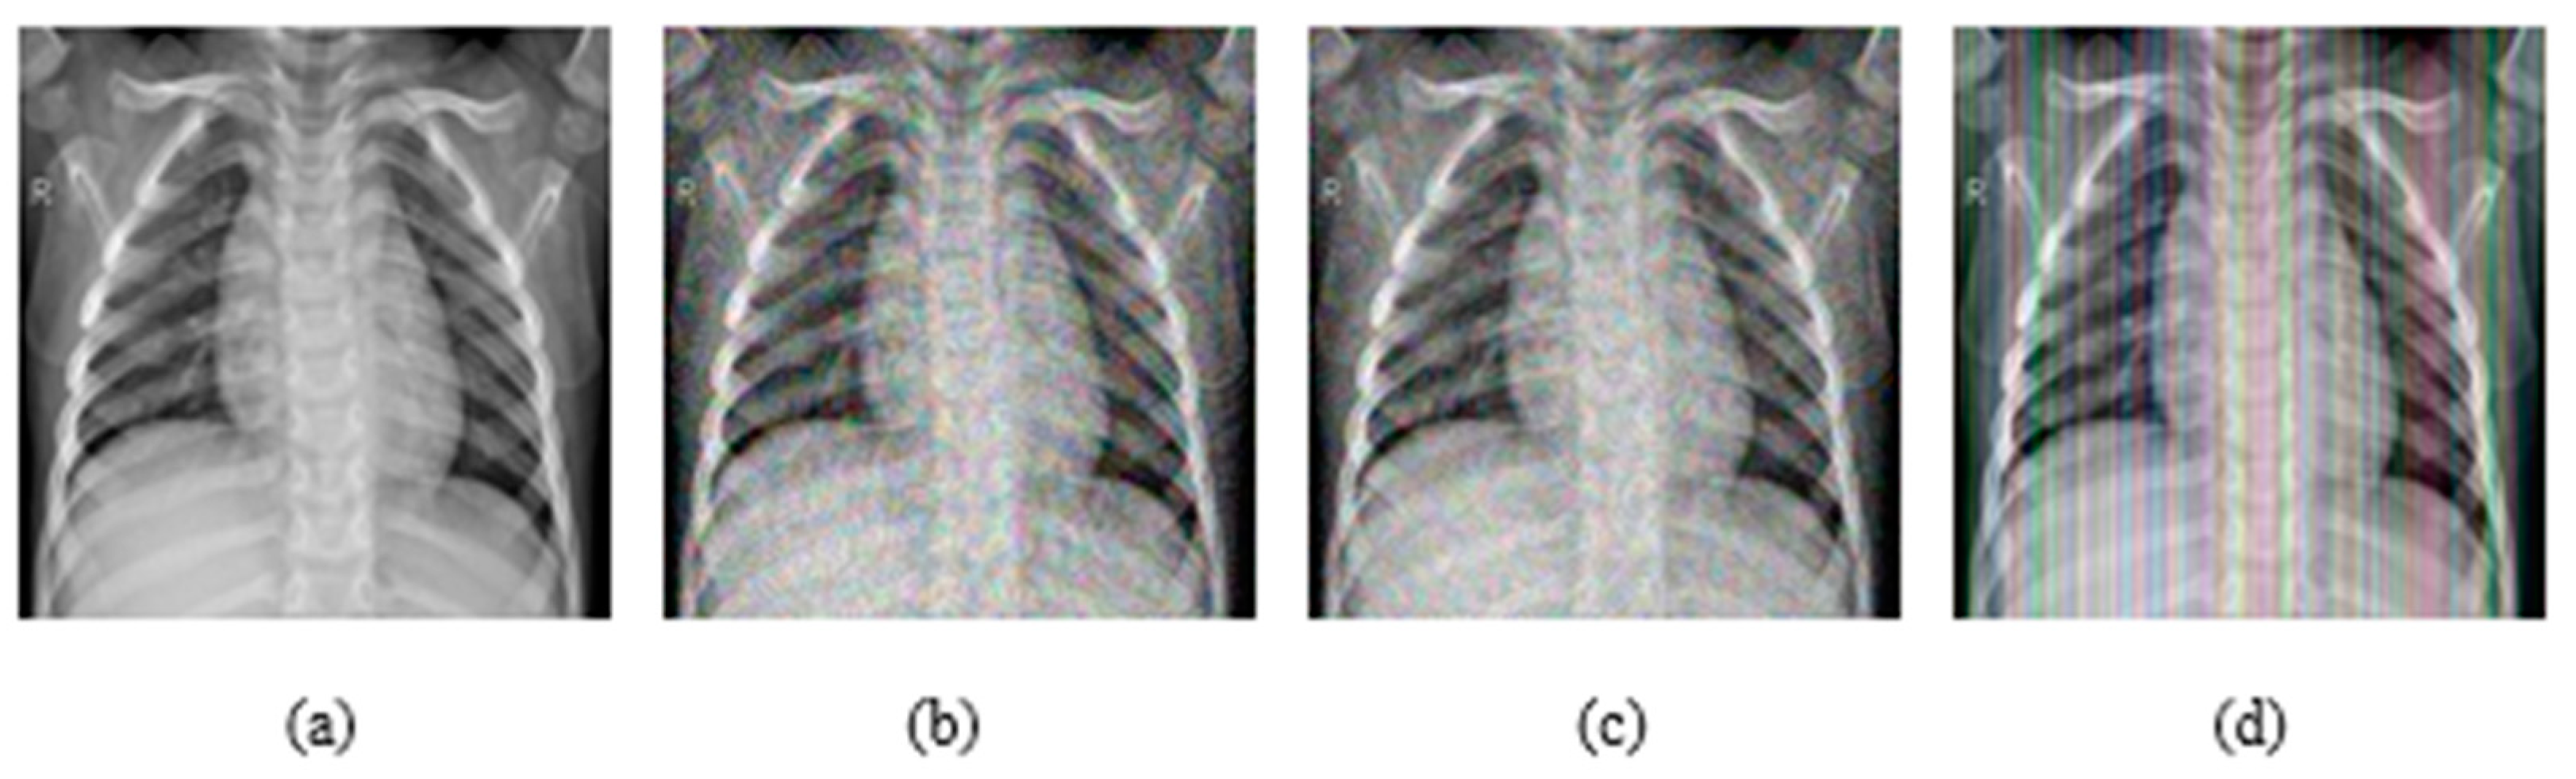

4.1. Datasets

4.2. Ablation Study

4.3. Results